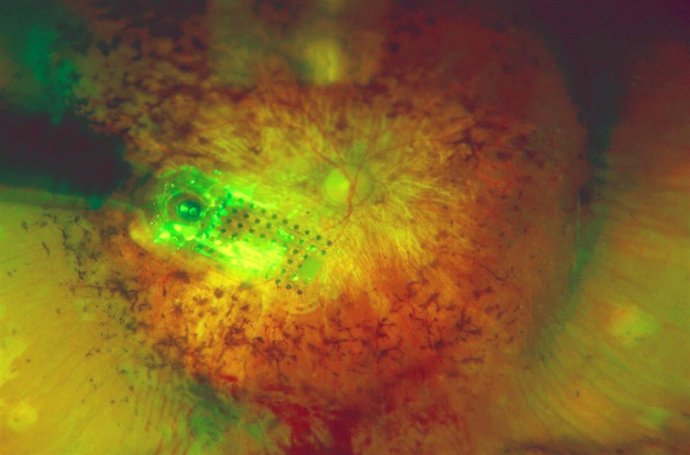

Un momento de la intervención para el implante del ojo biónico

EUROPA PRESS/HOSPITAL LA ARRUZAFA